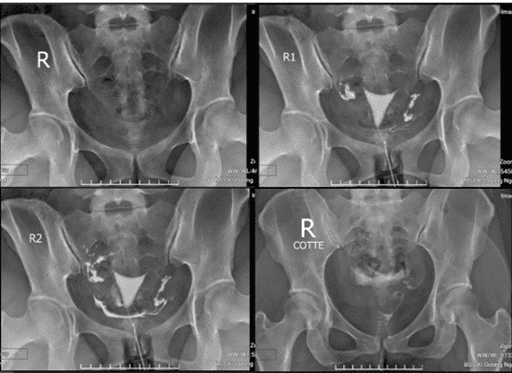

Chụp x quang tử cung vòi trứng để làm gì?

Chụp x quang tử cung vòi trứng là phương pháp đơn giản, chi phí rẻ, không gây đau đớn nhưng có hiệu quả rất tốt trong đánh giá tình trạng của buồng tử cung, ống dẫn trứng (vòi trứng, vòi tử cung) từ đó xác định được nguyên nhân gây vô sinh, khó mang thai.